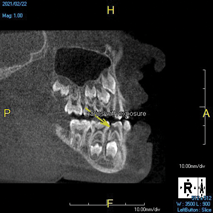

(10.) Tooth No. 31 in this 14-year-old patient does not exhibit caries. It is a “ghost tooth.” The lack of a periapical pathosis, the location of the tooth relative to the inferior alveolar nerve, and the development of tooth No. 32 are all visible in the CBCT image. These factors will aid the clinicians in developing a treatment plan to deal with this unusual internal resorption case.

Figure 10

Identifying the shape and location of the roots of teeth to be removed is critical to performing safe exodontia. Some clinicians virtually deconstruct teeth using CBCT images prior to actually sectioning and removing them. Being able to recognize pathoses and differentiate affected structures from normal structures is key in deciding what the treatment should be and when that treatment should be initiated (Figure 8 through Figure 10). The arena of the oral surgeon is larger than that of many general practitioners, involving the sinuses and condyles and other considerations in and around the entire mandible and maxilla. Certain fractures and other conditions that some general practitioners feel uncomfortable treating are often referred for evaluation and treatment by an oral surgeon. Because of this, oral surgeons require the most accurate and complete diagnostic information available. The American Academy of Oral and Maxillofacial Radiology recommends that "cross-sectional imaging be used for the assessment of all dental implant sites" and has stated that "CBCT is the imaging method of choice for gaining this information."18